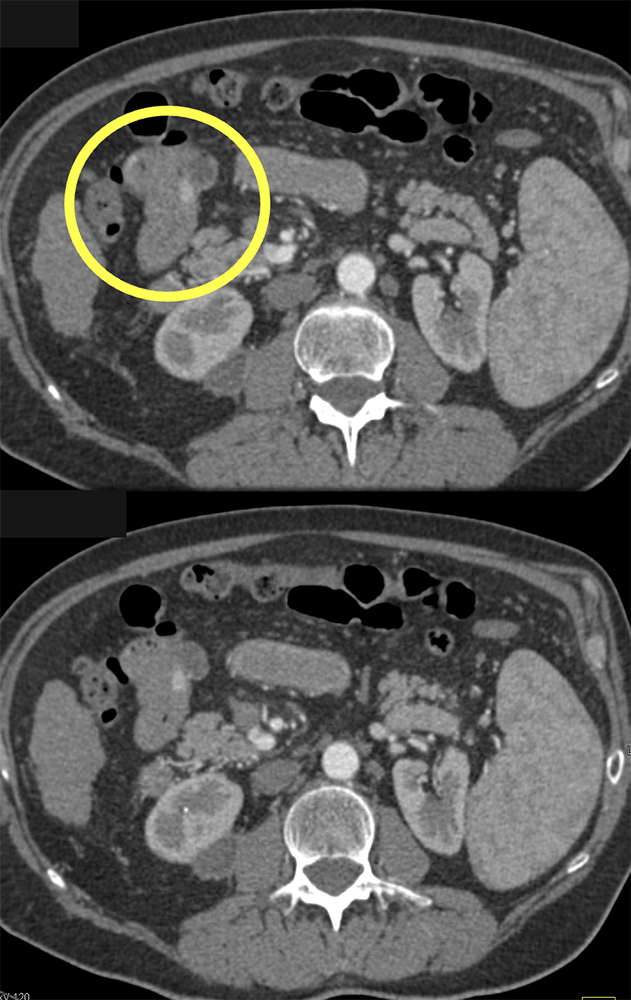

GI Bleed in Patient with Crohn’s and had Atrial Fib on Anticoagulants ![]() |

![]() |